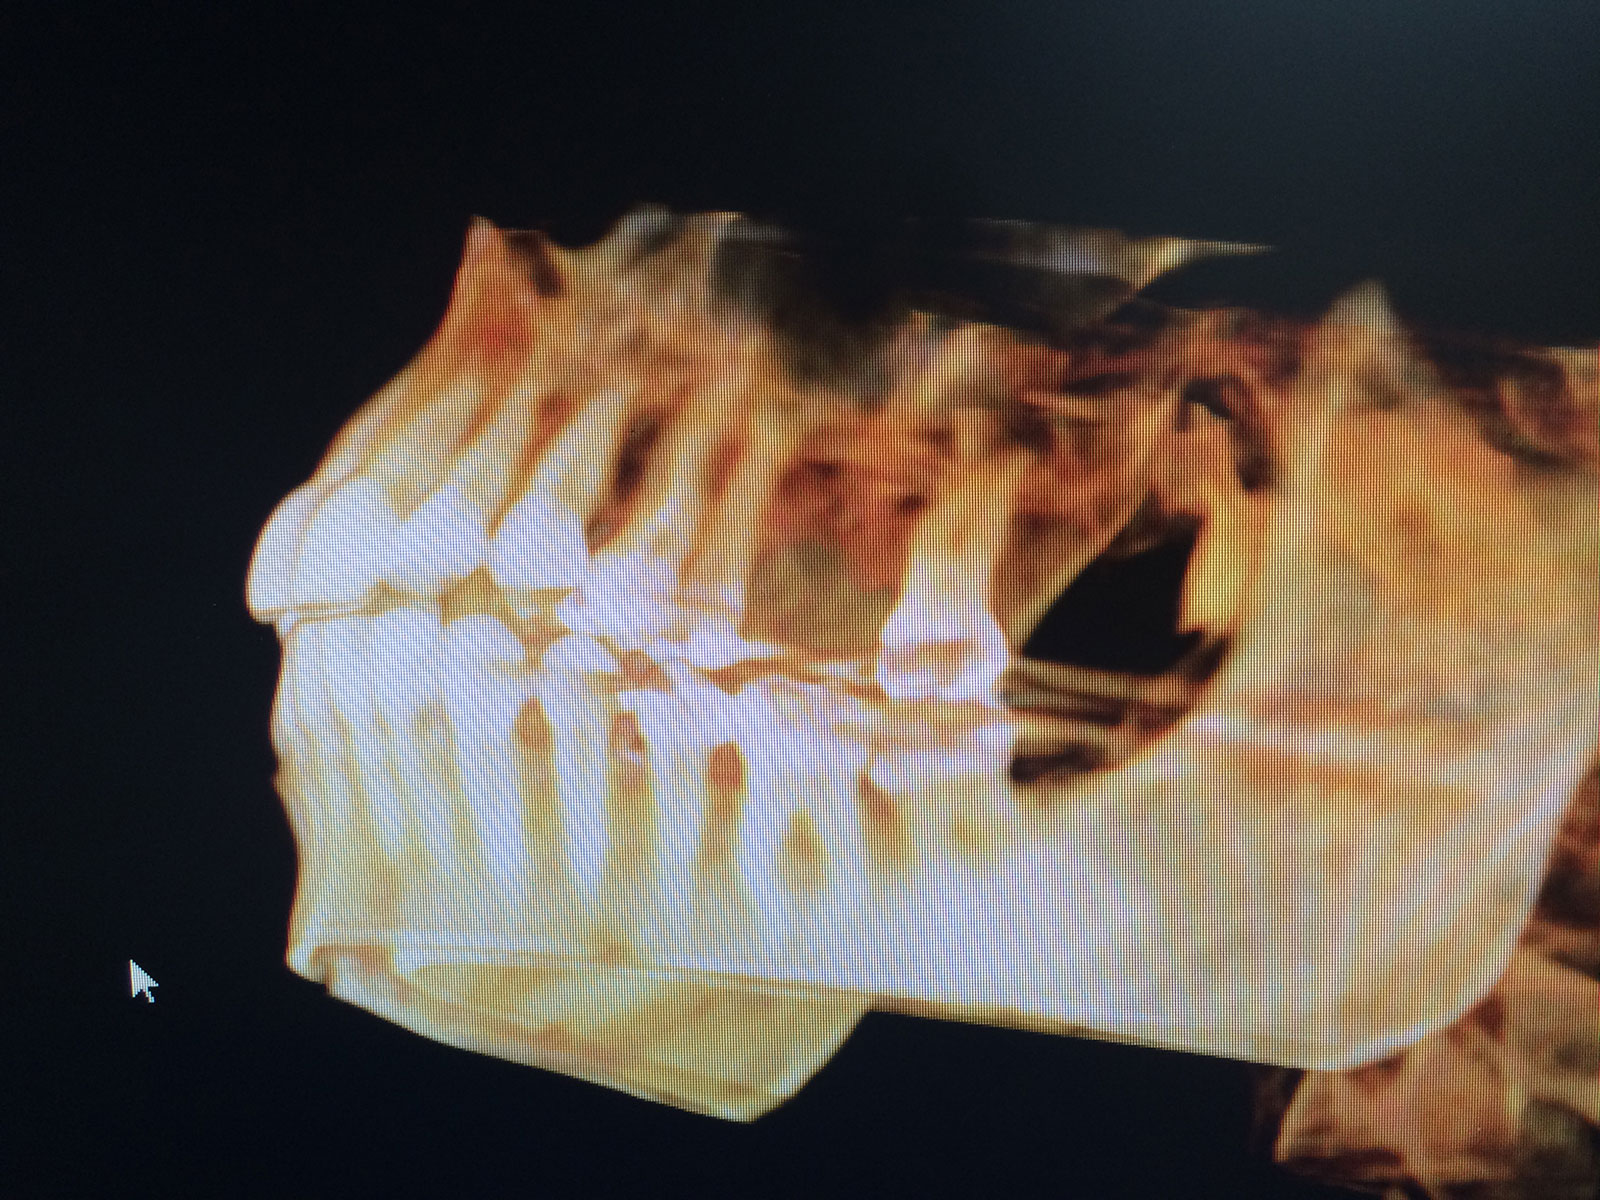

Sinus Grafting Procedures

A sinus grafting procedure, also known as a sinus augmentation, is for patients who have insufficient natural bone in the areas where dental implants are needed. They are long lasting, strong and sturdy, and fit and function like natural teeth. The procedure involves adding bone, either your own natural bone from another part of the body, from a donor or made of processed or synthetic bone material, and placing it below the sinus so that the implants can be placed. After the bone has healed and developed, usually around four to 12 months, the dental implants can be placed.

The photos on this website are from real surgeries performed by Dr. Ulloa. Due to the

graphic nature of the images and content, viewer discretion is advised.

Click to enlarge images